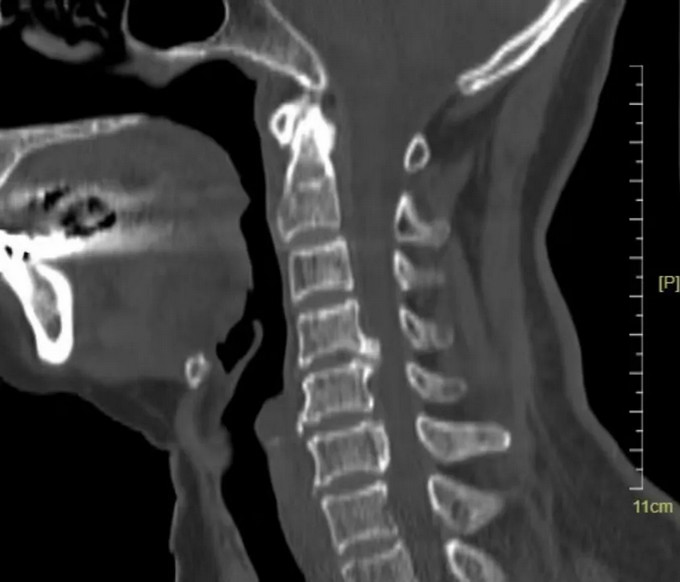

頸椎CT矢狀位

頸椎MRI矢狀位,可以看到患者的頸神經(jīng)被明顯壓迫